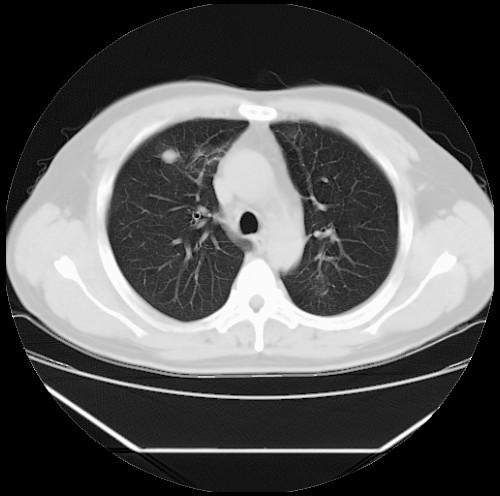

标题: CT22085:双肺多发结节

男,44岁,咳嗽,痰中带血2天。

病灶大部分位于胸膜下,结节大小相差不是很大,肺尖太干净。这种结核没见过,我认为可排除。

首先考虑转移,不除外肉芽肿、真菌感染。建议查其它。

除肺内及胸膜下可见多发大结节外,在肺小叶中心核、小叶间隔及支气管血管束上亦可见多方小结节,可以认为是随机分布。考虑转移可能性大。

仔细观察病灶形态,病灶边界部分清楚,结合临床症状,首先考虑转移,纵隔内多个肿大淋巴结影。

双肺血管纹理末端多发类圆形结节,边界光滑清晰 气管前腔静脉后淋巴结肿大

考虑转移瘤

沿血管分布,位于血管末端。转移瘤多见,血行性菌栓也可见到。

本例双肺多发类圆形高密度灶,边清,结合病史多考虑双肺多发转移改变,可以结合实验室检查。